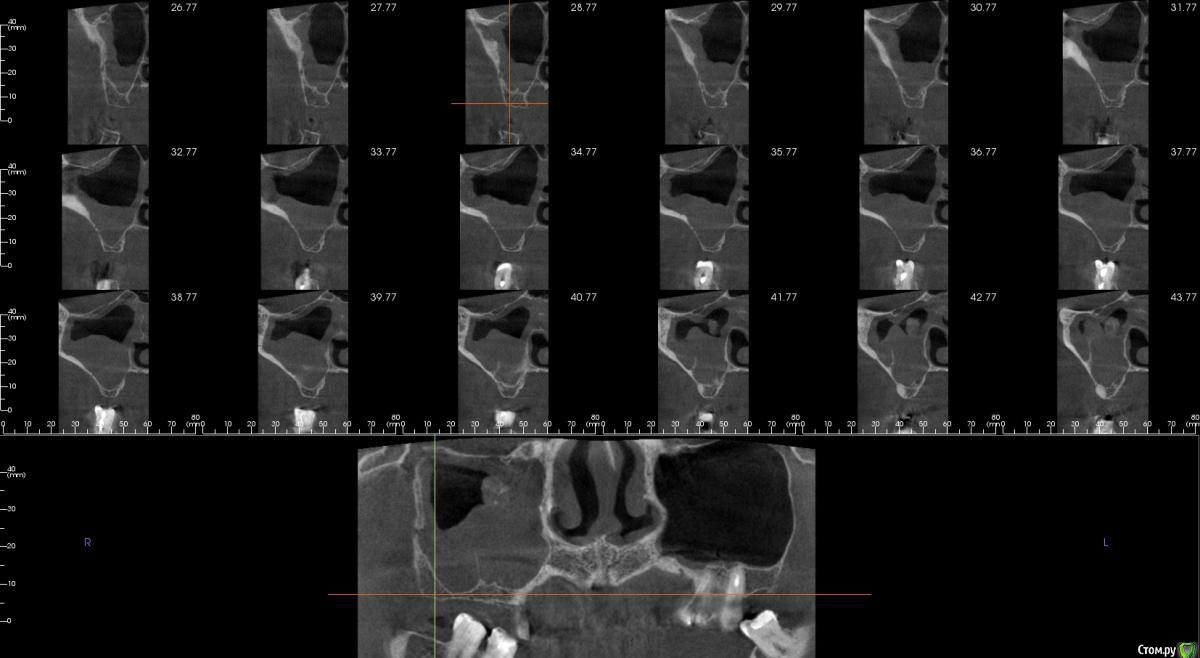

kamranchick Опубликовано 16 апреля, 2018 Автор Поделиться Опубликовано 16 апреля, 2018 Смотрел, и такое заключение дал. вот меня и смутило, в верхней трети около соустя вообще вкрапления какие то есть )) Ссылка на комментарий

Irouil Опубликовано 16 апреля, 2018 Поделиться Опубликовано 16 апреля, 2018 Смотрел, и такое заключение дал. вот меня и смутило, в верхней трети около соустя вообще вкрапления какие то есть ))Больше всего похоже на грибковое тело, и вкрапления эти намекают, и контуры затенения. Пунктировать не стал ЛОР это? 1 Ссылка на комментарий

kamranchick Опубликовано 16 апреля, 2018 Автор Поделиться Опубликовано 16 апреля, 2018 Больше всего похоже на грибковое тело, и вкрапления эти намекают, и контуры затенения. Пунктировать не стал ЛОР этоОтправил для санации, он написал вот это только( что ретенционная, но потом я внимательно начал крутить туда сюда и вот засомневался Ссылка на комментарий

Irouil Опубликовано 16 апреля, 2018 Поделиться Опубликовано 16 апреля, 2018 По большому счету; какая разница то? Вы же пациентку ради синус лифта (насколько я понимаю) отправляли, в таких условиях его не сделать. Там даже если соустье толщиною с пенис Трампа будет, все равно его ткани+отек перекроют после синуса. Так или иначе пазуху надо оперировать, только если ЛОР не считает что ретенционная киста - одонтогенная и пройдет при санации первичного очага) Ссылка на комментарий